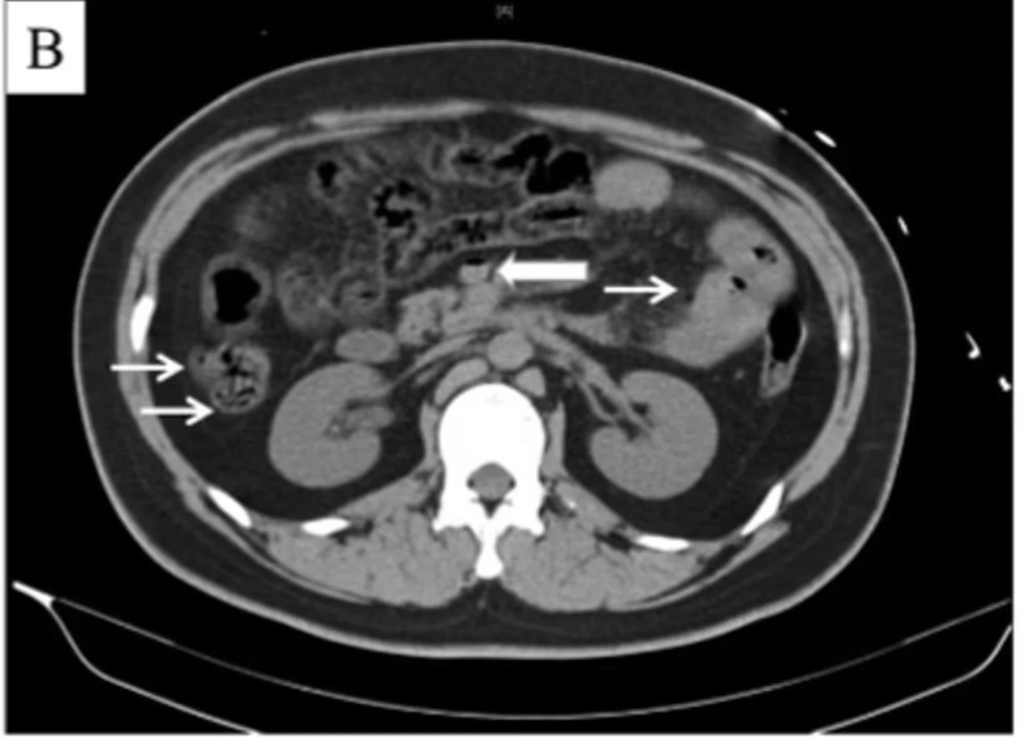

또 CT(컴퓨터단층촬영) 검사 결과 그의 장기와 간문맥(장과 간 사이의 혈관)에 평소와 달리 가스가 차 있었고, 간에서는 산소 공급 부족으로 장기가 손상되는 '허혈' 증세도 나타났다.

가는 화살표는 내장에 가스가 차 있음을 보여주고, 굵은 화살표는 내장에서 간으로 혈액을 운반해주는 혈관에 장간막 정맥에 가스가 차 있음을 보여준다. 국제 과학, 건강 전문 분석 회사 엘스비어(Elsevier).